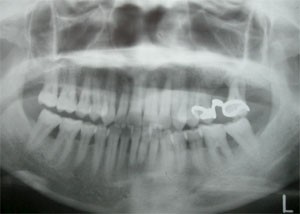

レントゲン2

患者さんはその後まじめに歯ブラシをし(セルフケア)定期的に歯科医院のチェックを受け(プロフェッショナルケア) 2005年3月のレントゲン像です。ほとんどもたないと思った歯も1本も抜くことなく、現在ご自分の歯で快適に食事をしています。